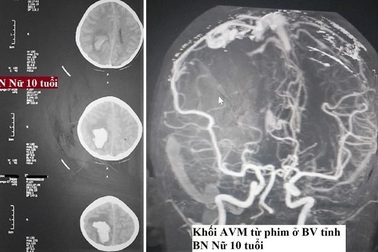

Cứu sống thần kỳ bệnh nhi 10 tuổi chảy máu nãoĐây là bệnh nhi nhỏ tuổi nhất Trung tâm Đột quỵ (Bệnh viện Bạch Mai) tiếp nhận, cứu sống thần kỳ sau khi em bị vỡ động tĩnh mạch não.